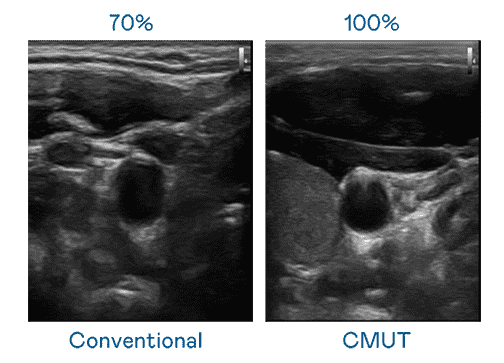

CMUT 技术是一种用电容式微机电元件来产生超音波讯号的技术。。。与传统 PZT 压电式技术相比,,,CMUT 频宽增加 30%,,更宽频的超音波讯号让影像解析度大幅提升,,,是实现高影像品质医疗超音波扫描、、、、促进精准医疗发展的关键技术。。。。

大频宽带来超清晰影像

超音波影像的解析度高低,,,,首先取决于探头能发出的讯号频宽。。CG电子 CMUT 可提供高清晰的超音波讯号,,,,提供高频宽、、、高灵敏度、、、、影像纹理细节更高的超音波影像,,,协助医护人员缩短影像判读时间及利用精准的医疗影像进行诊断。。。。